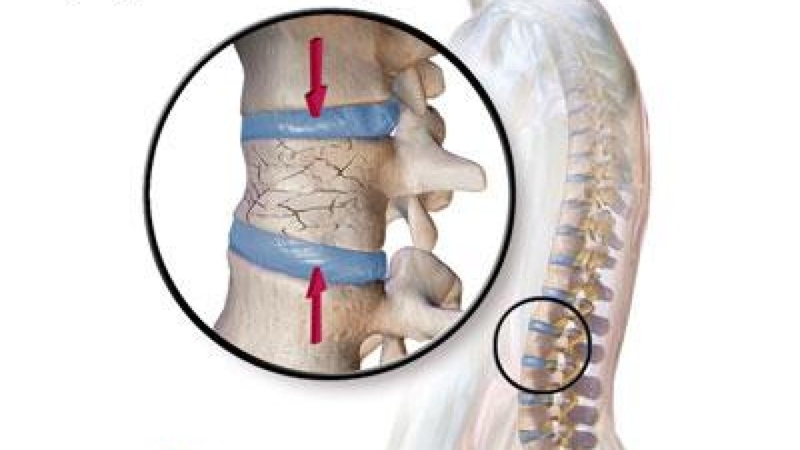

Bất kỳ tổn thương nào ở đốt sống cổ cũng có thể gây ra hậu quả nghiêm trọng bởi chúng có tủy sống chạy qua lõi và đảm nhận nhiệm vụ kết nối hệ thống thần kinh trung ương giữa bộ não với toàn bộ cơ thể. Tổn thương ở tủy sống có thể dẫn đến tê liệt hoặc tử vong vô cùng nguy hiểm. Gãy xương cổ hay gãy đốt sống cổ là tình trạng nứt vỡ của bất kỳ một trong bảy đốt sống ở cổ.

Gãy xương cổ là tình trạng nứt vỡ các đốt sống cổ